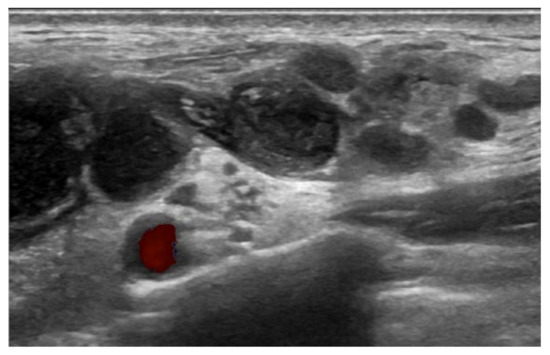

Figure 2.

Ultrasonography scan of COVID-19 vaccination-induced lymphadenopathy patient revealed multiple enlarged LNs, with conglomeration in the left supraclavicular area.

Ultrasonography may be the most simple and non-invasive diagnostic tool in cases of extrapulmonary TB with LN enlargement. Typical sonographic features of TB lymphadenitis are multiple, irregular, enlarged, and conglomerating lymph nodes that have a tendency toward fusion [25], which is the exact finding in our case. 18F-FDG PET/CT can also contribute to earlier extrapulmonary TB detection particularly in multisite involvement cases with an average maximum standardized uptake value (SUVmax) of 5.3–13.4 [26,27]. Multiple hypermetabolism has an SUVmax of 5.1–9.5 in cases where the patient presents a typical characteristic of extrapulmonary TB in 18F-FDG PET/CT. Another simple option prior to biopsy for screening would be the tuberculin skin tests, for which positive results should be further confirmed by in vitro enzyme immunoassay tests [28].